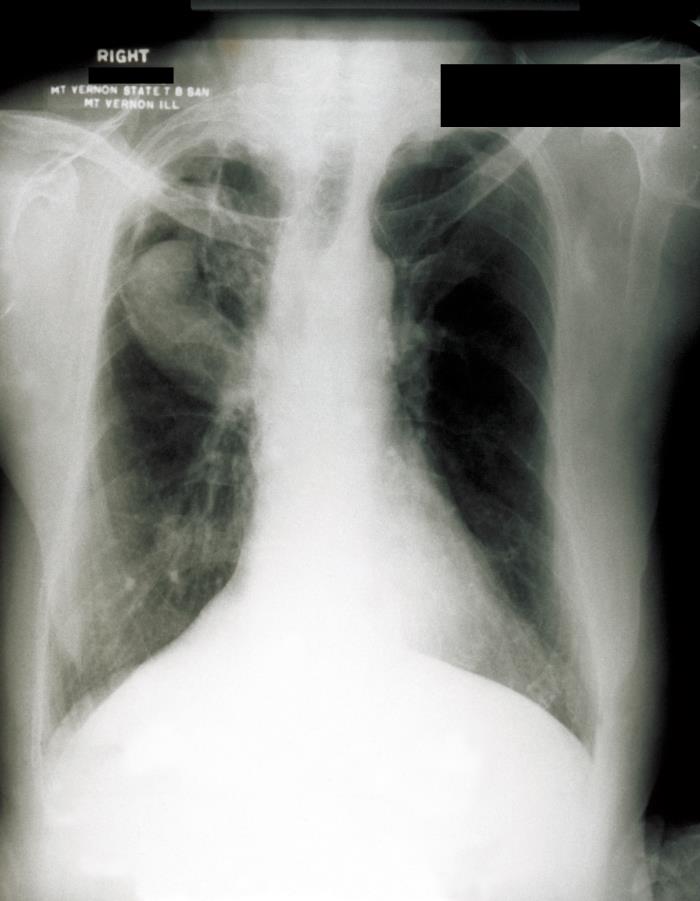

This image depicts an anteroposterior (AP) chest radiograph of a patient in Mount Vernon, Illinois, who had presented with a case of pulmonary histoplasmosis. Note the presence of a radiolucency in the patient’s right upper lobe, which was diagnosed as a probable aspergilloma, or fungus ball.